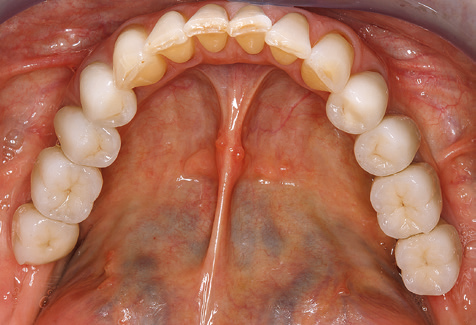

Un paziente di 52 anni si è presentato nella nostra clinica per la prima volta nel 2004 a seguito della perdita dei denti nel terzo quadrante, esprimendo il desiderio di un nuovo restauro protesico. La diagnostica parodontale e radiologica ha rivelato la necessità di un ampio trattamento parodontologico. Inoltre, ai denti 48, 28 e 27 è stata attribuita una prognosi molto scarsa e sono stati successivamente estratti (Fig. 1). A seguito del trattamento periodontologico sistematico completato con successo, è stato inserito una protesi dentale fissa con l'inserimento di cinque impianti nelle regioni dentali 35, 36, 37, 46 e 47. Il trattamento protesico dei denti naturali è stato effettuato con corone rivestite in ceramica di biossido di zirconio; gli impianti two-piece composti da abutment singoli in biossido di zirconio e corone similmente rivestite in ceramica di biossido di zirconio (base Cercon colorata, Dentsply Sirona Lab). L'inserimento definitivo del restauro protesico è avvenuto nel 2005.

A causa della presenza di problematica parodontale, SPT è stata eseguita ogni tre mesi nei primi anni successivi all'inserimento. Il paziente ha dimostrato un alto grado di motivazione e una buona costanza. Le profondità di tasca registrate ogni anno hanno rivelato una situazione parodontale stabile con un indice BOP inferiore al cinque per cento. Sulla base della situazione parodontale stabile e della buona collaborazione da parte del paziente, l'intervallo di richiamo è stato esteso ogni sei mesi a partire dal sesto anno dalla fase della funzione protesica. A seguito della modifica dell'intervallo di richiamo, la rispettiva documentazione annuale dello stato parodontale ha continuato a rivelare una situazione parodontale stabile senza aumento della profondità della tasca e un indice BOP inferiore al cinque per cento (Fig. 2a eb).

Il controllo decennale non ha rivelato alcuna indicazione dell'avanzamento della perdita di attaccamento clinico o della perdita di sostanza ossea perimplantare (Fig. 3).

Un'assistenza standardizzata e regolare a misura di rischio nell'ambito di SPT è la chiave per il successo del trattamento clinico a lungo termine nei pazienti con situazione periodontale compromessa. Ciò è particolarmente vero per i pazienti a cui vengono applicati impianti dopo il trattamento parodontale completato con successo (Fig. 11a e b).